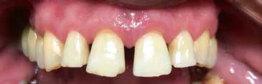

VorherNachher

Beispielhaft nun die Anwendug von OXYSAFE am Frontzahn

11. Die Sondierungstiefe beträgt sowohl mesial als auch distal 7 mm an Zahn 11 und es liegt eine Blutung vor. Es liegt ein vertikaler Knochenverlust vor.